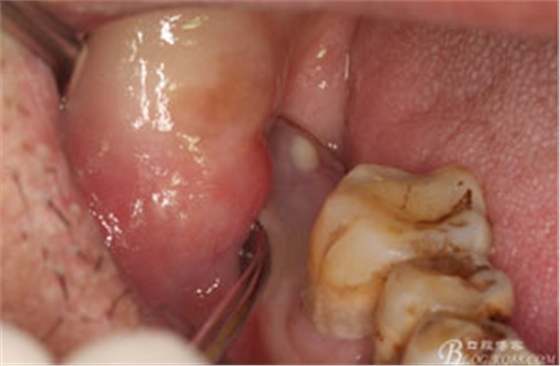

圖1。術(shù)前檢查的口內(nèi)像:48區(qū)域的位置有一瘺口。捫診溢膿。48未萌出。